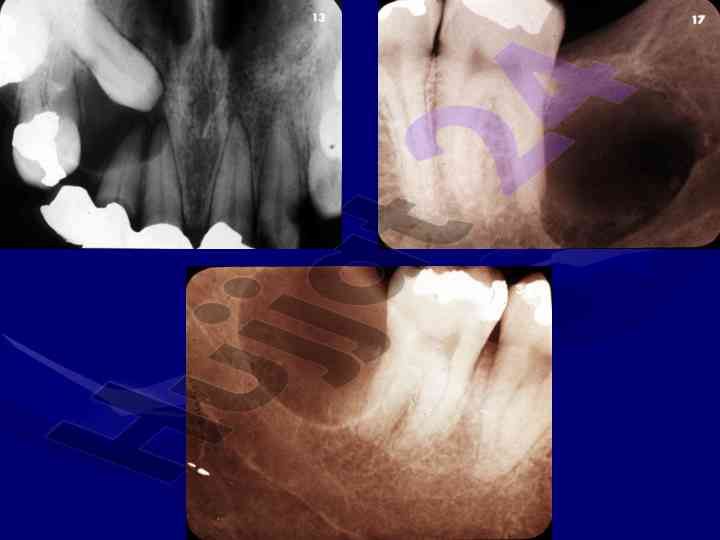

Диагностика и характеристики кист чло

Данная лекция охватывает диагностические критерии, локализацию и структуру кист и опухолей челюстно-лицевой области, включая одонтогенные и неодонтогенные кисты.